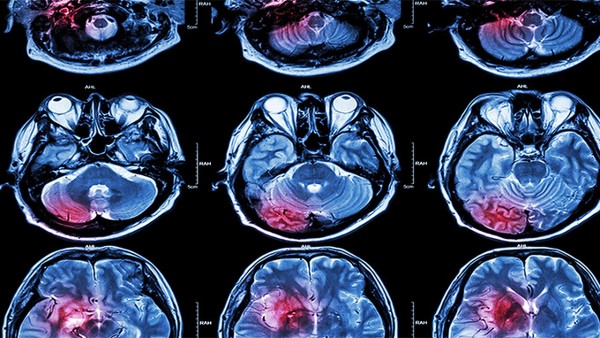

脑梗塞是由脑血管病变引起的血管闭塞,引起局灶性脑缺血引起的脑组织不可逆性损害。急性脑梗塞患者应尽快送往有检查和治疗条件的医院,搬运过程中应注意平卧,保护呼吸顺畅。急性脑梗塞的治疗与患者的个人状况和药物治疗是否及时有关。